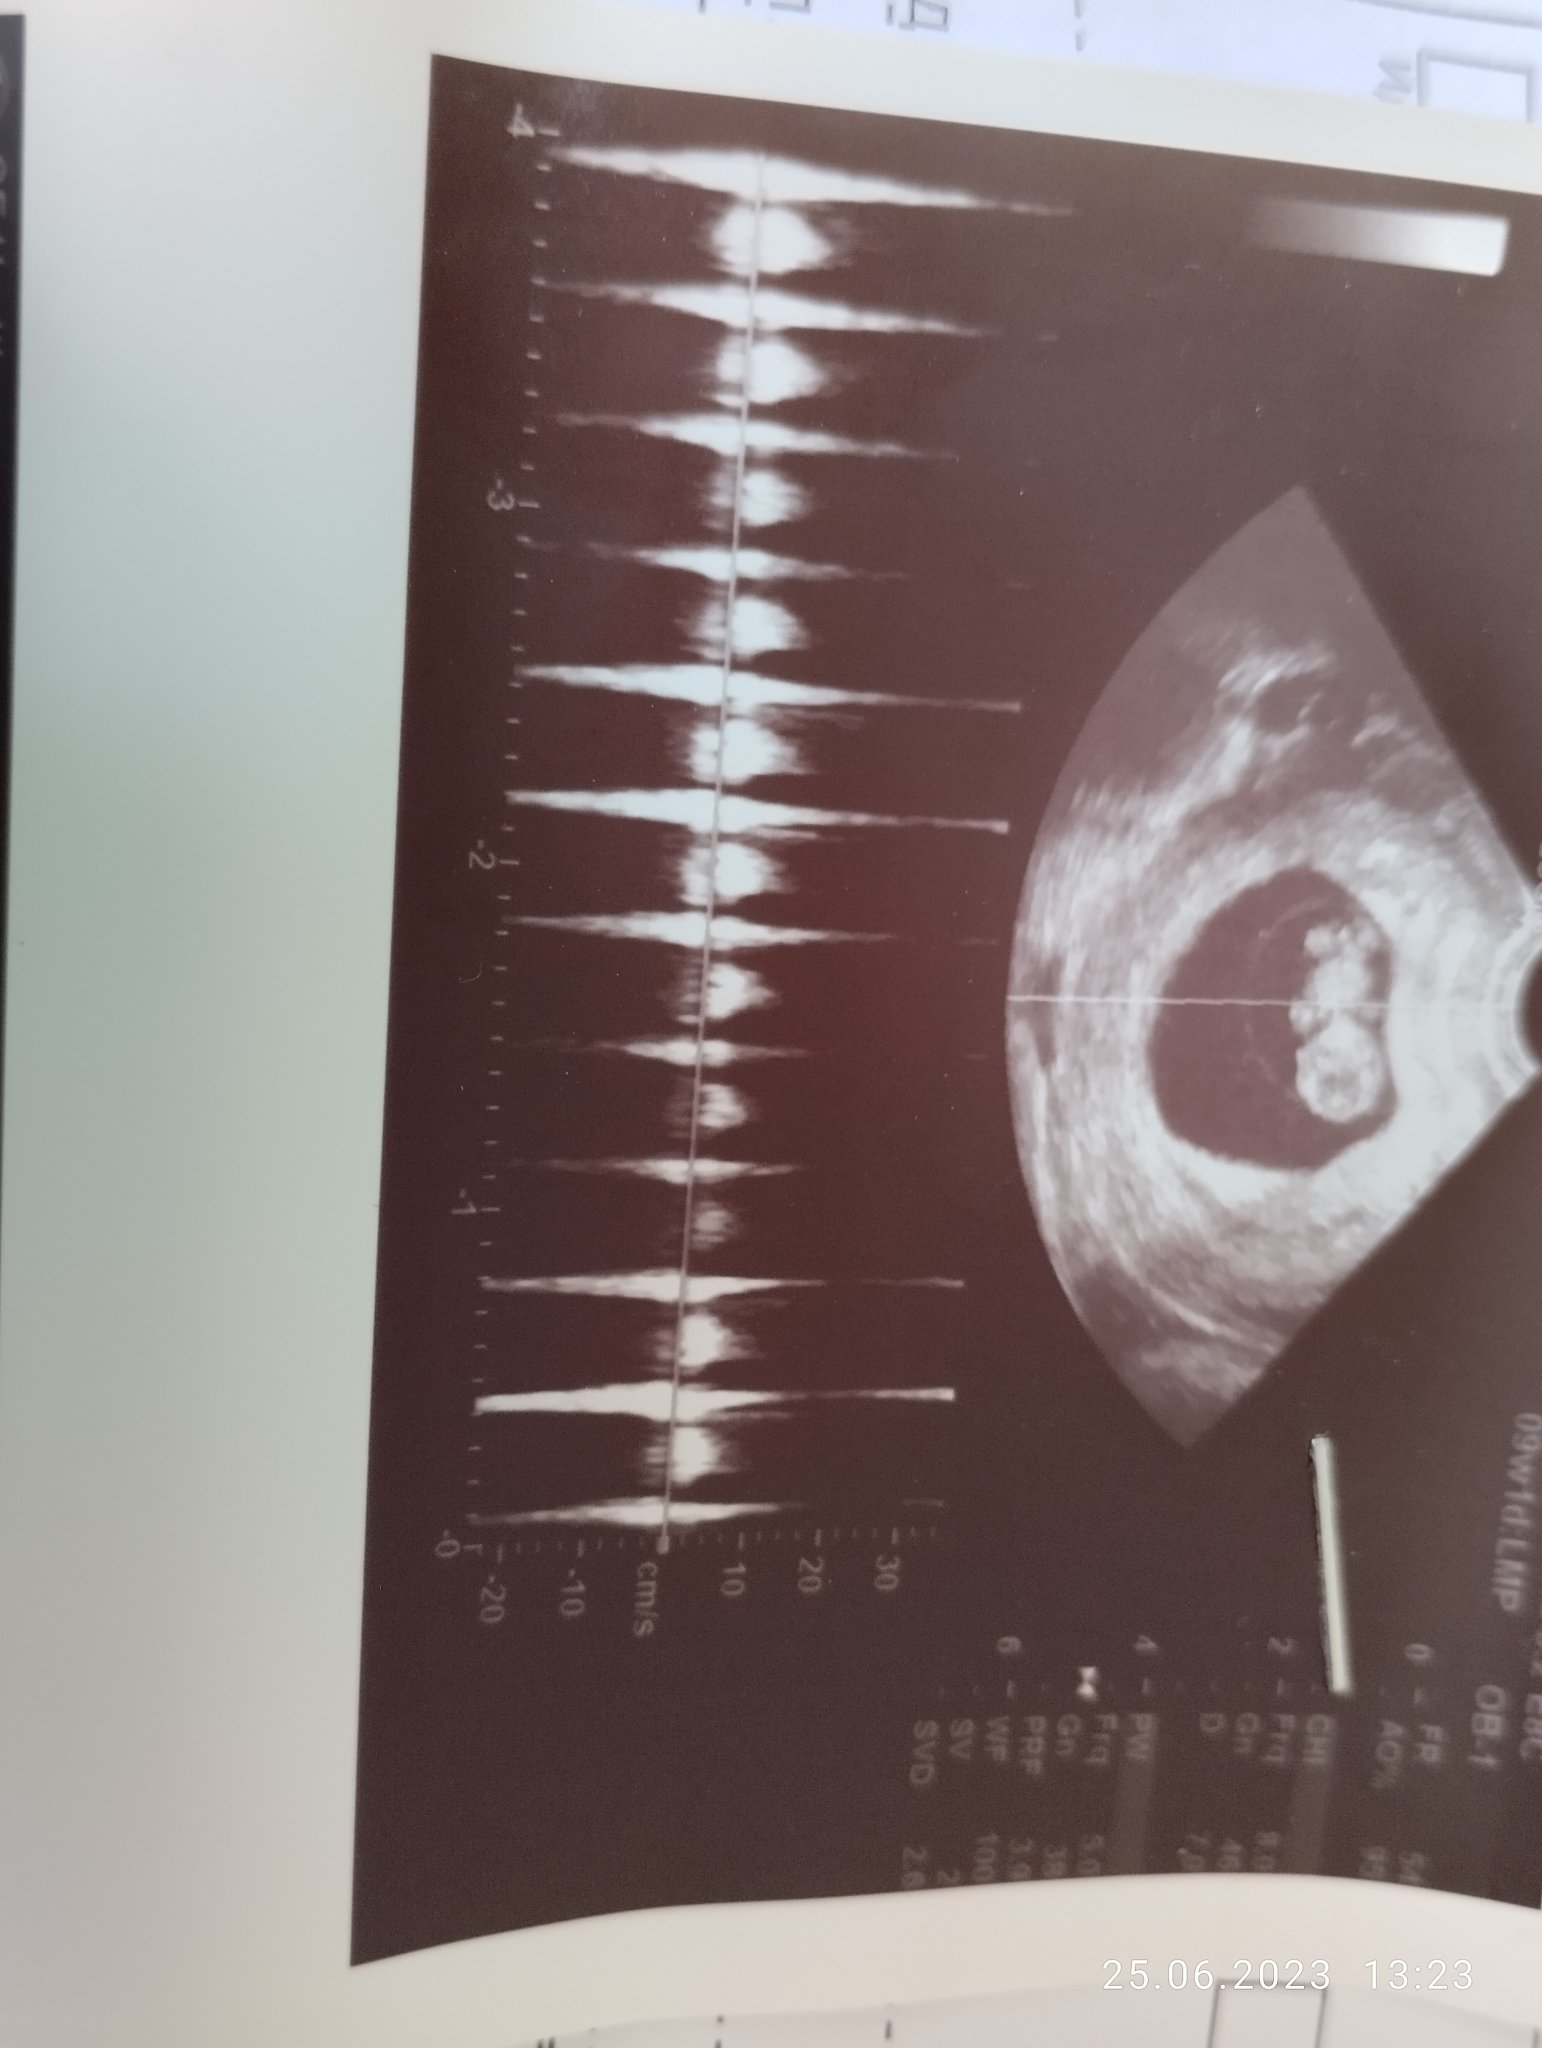

Извинете ме за глупавия въпрос, ама къде пише на ехографската снимка колко е пулса? Моята докторка нищо не ми е казвала за него. Така изглежда снимката

Аз поне не виждам да пише. Попринцип си избират участък докторите и измерват честотата, би трябвало да е казал доктора какъв е пулса, ако не явно е видял че е добре и не е споменал нищо.

Аз мога да кажа в 9г.с+6 дни как е бил 169 удара в минута.

При мен пише пулс на такава снимка, горе в дясно. Най-вероятно зависи от апарата. Мен ме гледат на Voluson.